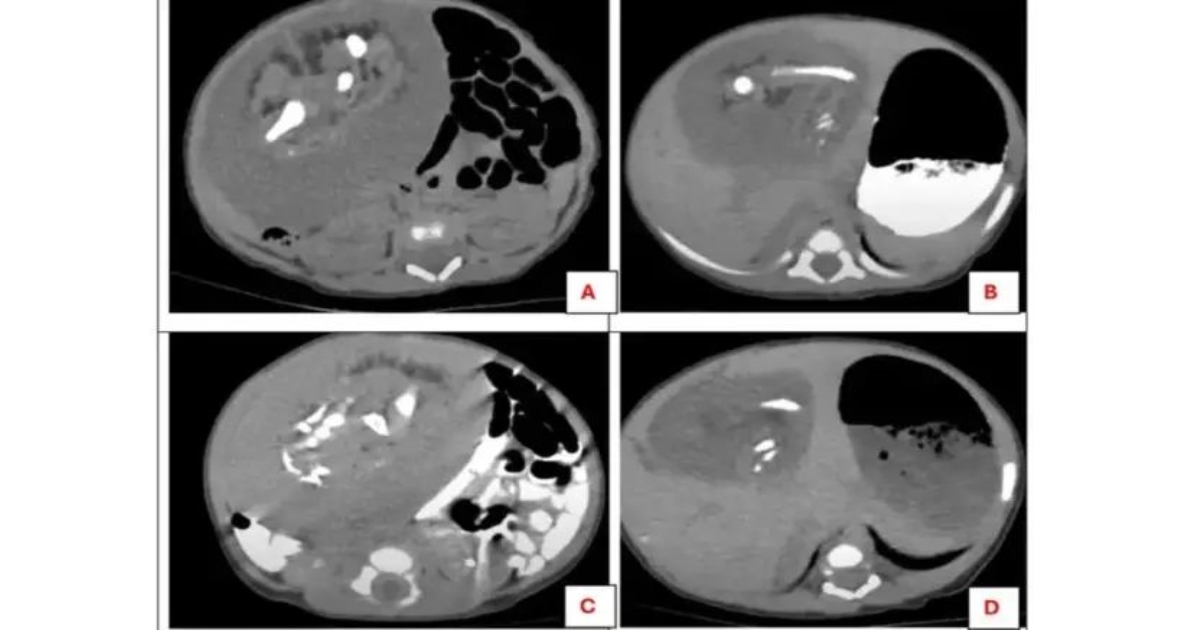

அல்ட்ராசவுண்ட் சோதனையில், 8×6 செ.மீ அளவிலான மென்மையான திண்மப்பொருள் கண்டறியப்பட்டது. அதன் பின் மேற்கொண்ட கம்ப்யூட்டர் டோமோகிராஃபி (CT) ஸ்கேன் மூலம் நீண்ட எலும்புகள், விலா எலும்புகள், முதுகெலும்பு, இடுப்பு எலும்புகள் மற்றும் மென்மையான திசுக்களுடன் ஒரு அமைப்பு இருப்பது தெரியவந்தது. இது ‘ஃபீடஸ் இன் ஃபீடு’ (Fetus in Fetu) எனப்படும் அரிய நிலை என மருத்துவர்கள் உறுதிப்படுத்தினர்.

இந்த அதிசயமான நிலை அக்டோபர் மெடிக்கல் ஜர்னலில் வெளியிடப்பட்டது. இரண்டு மணி நேரம் நீடித்த அறுவை சிகிச்சையின் மூலம் அந்த அமைப்பு வெற்றிகரமாக அகற்றப்பட்டது. நுண்ணோக்கி ஆய்வில், அது முழுமையான கரு திசுக்கள், தோல் மற்றும் குடல் திசுக்களை கொண்டிருந்தது உறுதி செய்யப்பட்டது.